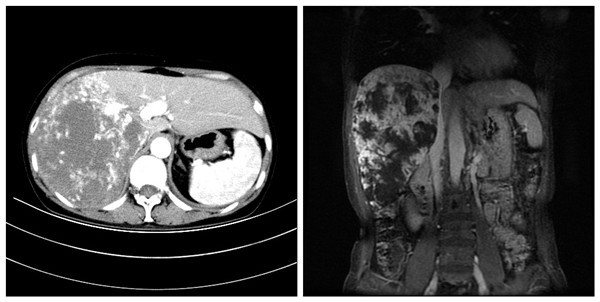

现年50岁的孙女士家住陕西省铜川市。两月前,孙女士感到右上腹疼痛,但由于平素身体状况良好,未予重视。后来上述症状持续不缓解,孙女士开始重视了。在当地医院就诊,行上腹部增强CT示:肝右叶巨大肿块影,多期扫描呈斑片状结节样渐进性强化,考虑肝右叶巨大血管瘤。这一检查结果对于没有医学背景的孙女士一家如同晴天霹雳!“血管瘤!是不是恶性肿瘤!”种种猜想萦绕在孙女士的心头。后来孙女士一家通过各种渠道,听闻西安交大二附院普通外科黎一鸣教授在肝血管瘤治疗方面有颇深的造诣,慕名而来。

孙女士入院后接受了完整的术前检查及评估,而其结果回报提示肝右叶肿块占位明显,邻近结构受压移位,下腔静脉肝后段受压,管腔明显变窄。黎一鸣教授团队分析认为:肿瘤巨大,若要完整切除肿瘤,需要仔细分离第二、第三肝门,必要时需行下腔静脉人工血管重建。且术中需阻断肝门,手术必须以最快的速度精细的完成,以避免术后患者出现肝功能障碍,手术难度极大。

面对如此高风险的手术,黎一鸣教授、刘清峰副教授、吉鸿副教授、陆宏伟教授等经过认真讨论,组织科室专家反复研究,制定了严密的围术期治疗计划,并与患者家属充分沟通病情及治疗方案。万事俱备,黎一鸣教授团队于2018年4月11日在输血科、麻醉手术科医务人员的大力配合下,在全麻下为该患者实施了肝巨大血管瘤切除术。术中见肿瘤约30*25*20cm大小,已占据整个肝右叶,其病情与术前评估一致。手术历时3小时顺利完成,术中出血量少,术野清晰。黎一鸣教授高超的肝胆外科造诣保证了该项高难度手术的顺利实施。术后患者恢复顺利,拟于近日出院。